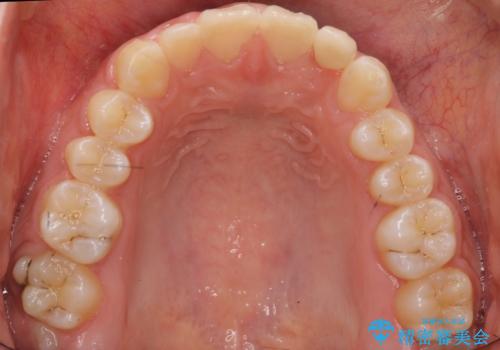

前歯のすきま 矯正治療とセラミックで小さな歯を形良く

- 前歯のすきまを気にして来院。

左上の2番が生まれつき小さく、スペースが余っていました。

右上の2番もやや小さめでしたが、相談の上、左上2番のみセラミックで形を整えることとしました。

そのほかの隙間はマウスピース矯正で閉じることにしました。

- 総額99万円 (矯正治療:85万円 左上2:ジルコニアクラウン スペシャル 13万円、仮歯 1万円)費用は治療当時の料金となります

当初はワイヤー矯正を希望されていましたが、右上7番の頬側に咬頭があり、ブラケットを貼ることが難しいため、こちらからマウスピース矯正をお勧めしました。